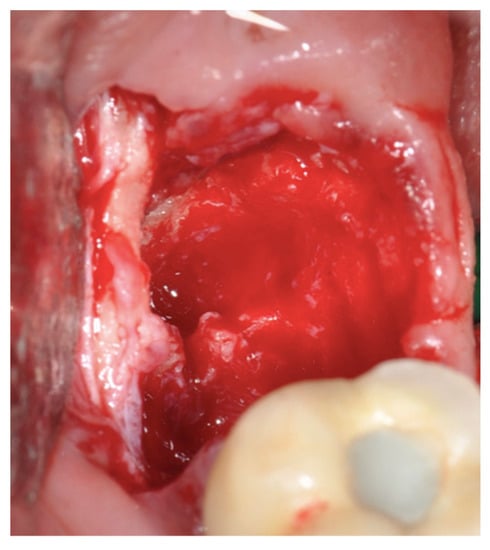

2.2. Surgical Technique